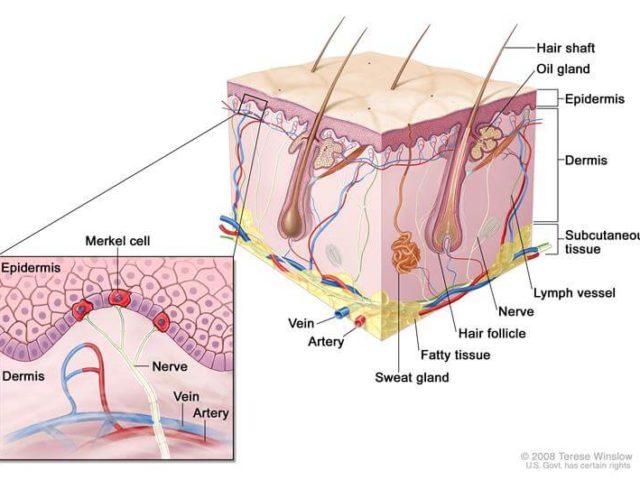

The Food and Drug Administration (FDA) has approved the immunotherapy drug avelumab (Bavencio®) for the treatment of some patients with a rare and aggressive skin cancer known as Merkel cell carcinoma. It is the first FDA-approved treatment for this disease. The approval was based on results from a clinical trial that included 88 patients with metastaticMerkel cell carcinoma who had previously been treated